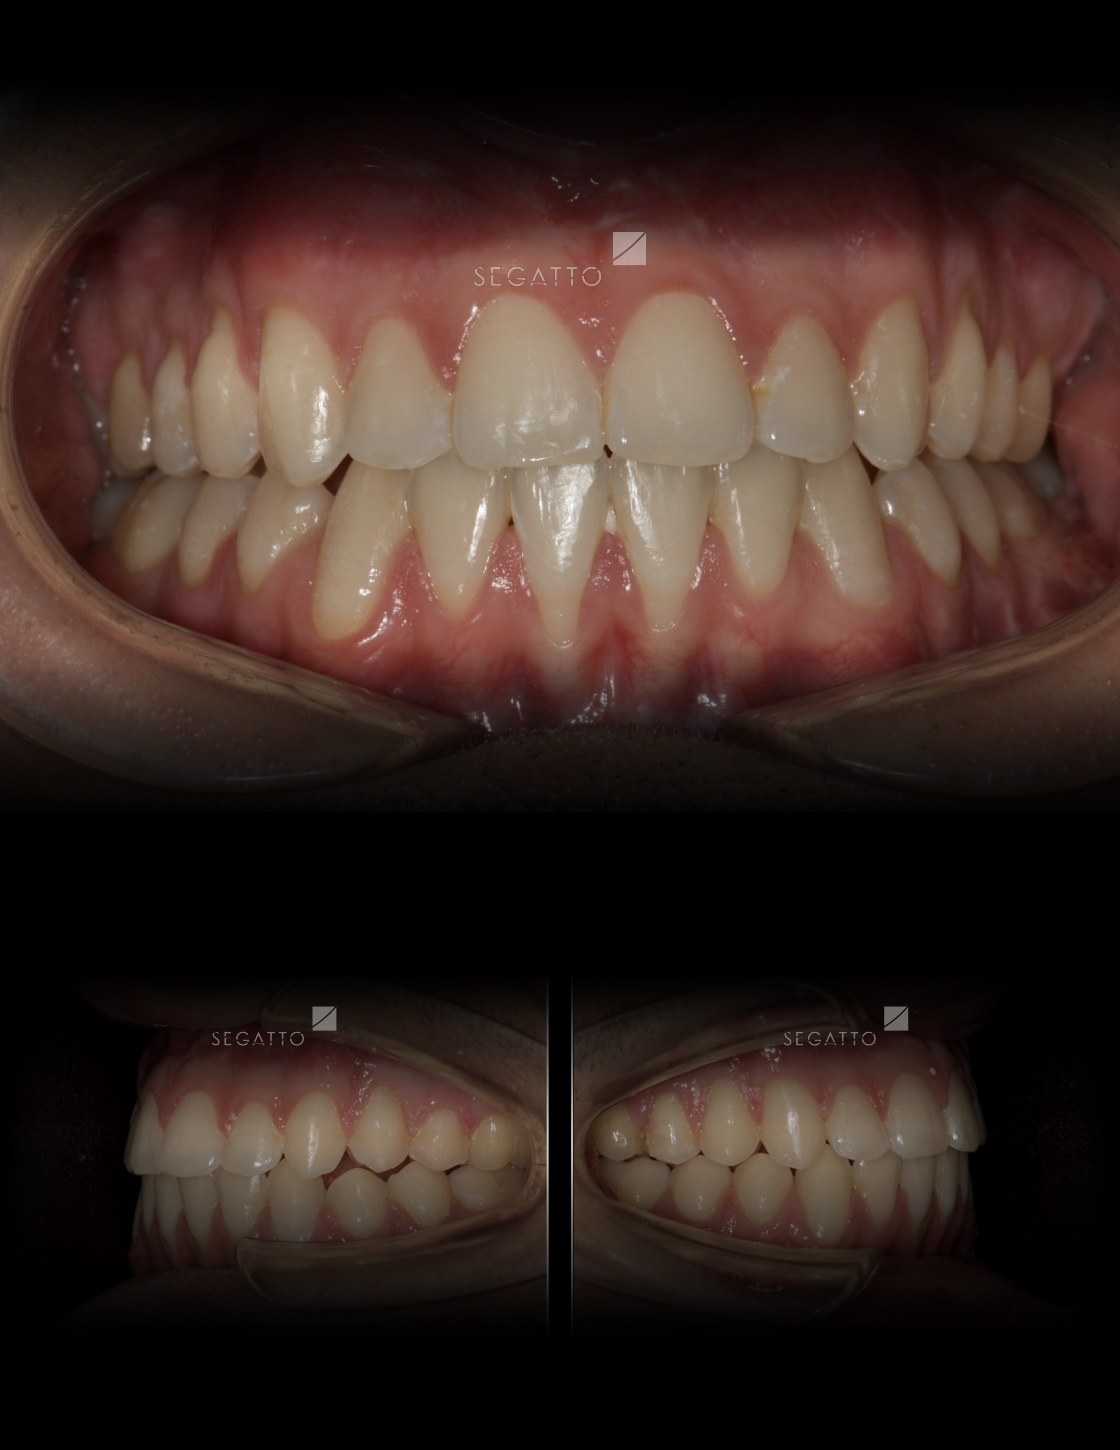

Orthodontics

Cases